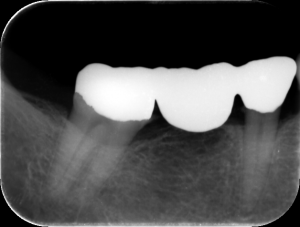

| ブリッジ | インプラント |

![]() |